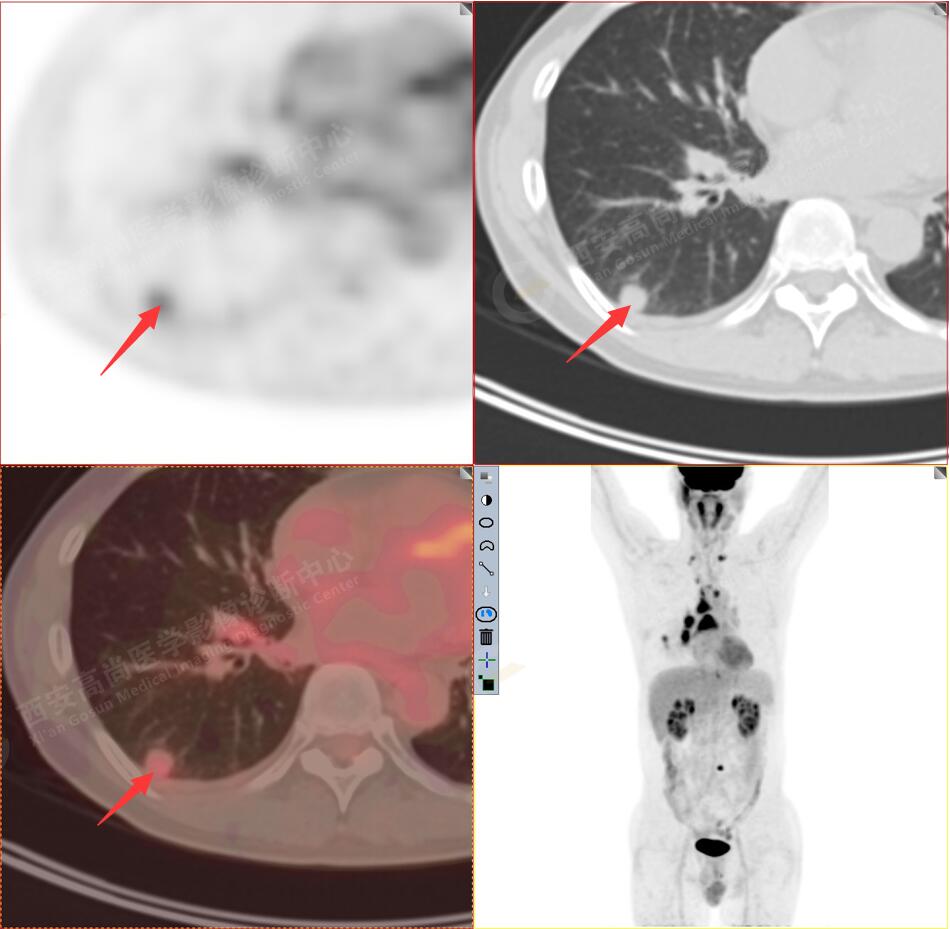

1.以下為肺內(nèi)原發(fā)灶

1.右肺下葉后基底段軟組織結(jié)節(jié)(約1.5cm×1.2cm),與相鄰后胸膜分界不清,呈FDG代謝異常增高,結(jié)合病理,符合肺腺癌伴鄰近胸膜侵犯。